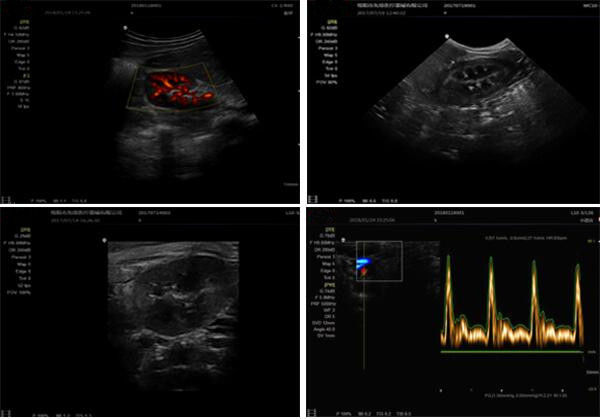

4d Ultrasound Equipment Portable Ultrasound Scanner With Phased Array Probe of Center Frequency 3MHz

5000E color doppler ultrasound system adopts the imaging technology of Biomedical high-end products.

It was released as a powerful and versatile imaging platform with a futuristic design.Elegant appearence

and compact, yet featuring comprehensive applications for abdomen, obstetrics, cardiac,gynecology,

small parts and urology, 5000E provides the best solution for ultrasound imaging through outstanding

performance.

| Display mode | B,B/B,M,B/M,CFM,CMF/B,PDI,B/PW,CW etc mode |

| Application mode | abdomen, kidneys, urinary system, obstetrics, gynecology, pelvic, small organ, muscle tissue, organ, breast, heart and other 11 kinds of models |

| Image mode | digital beam forming, tissue harmonic imaging |

Images

4d Ultrasound Equipment Portable Ultrasound Scanner With Phased Array Probe of Center Frequency 3MHz Images |